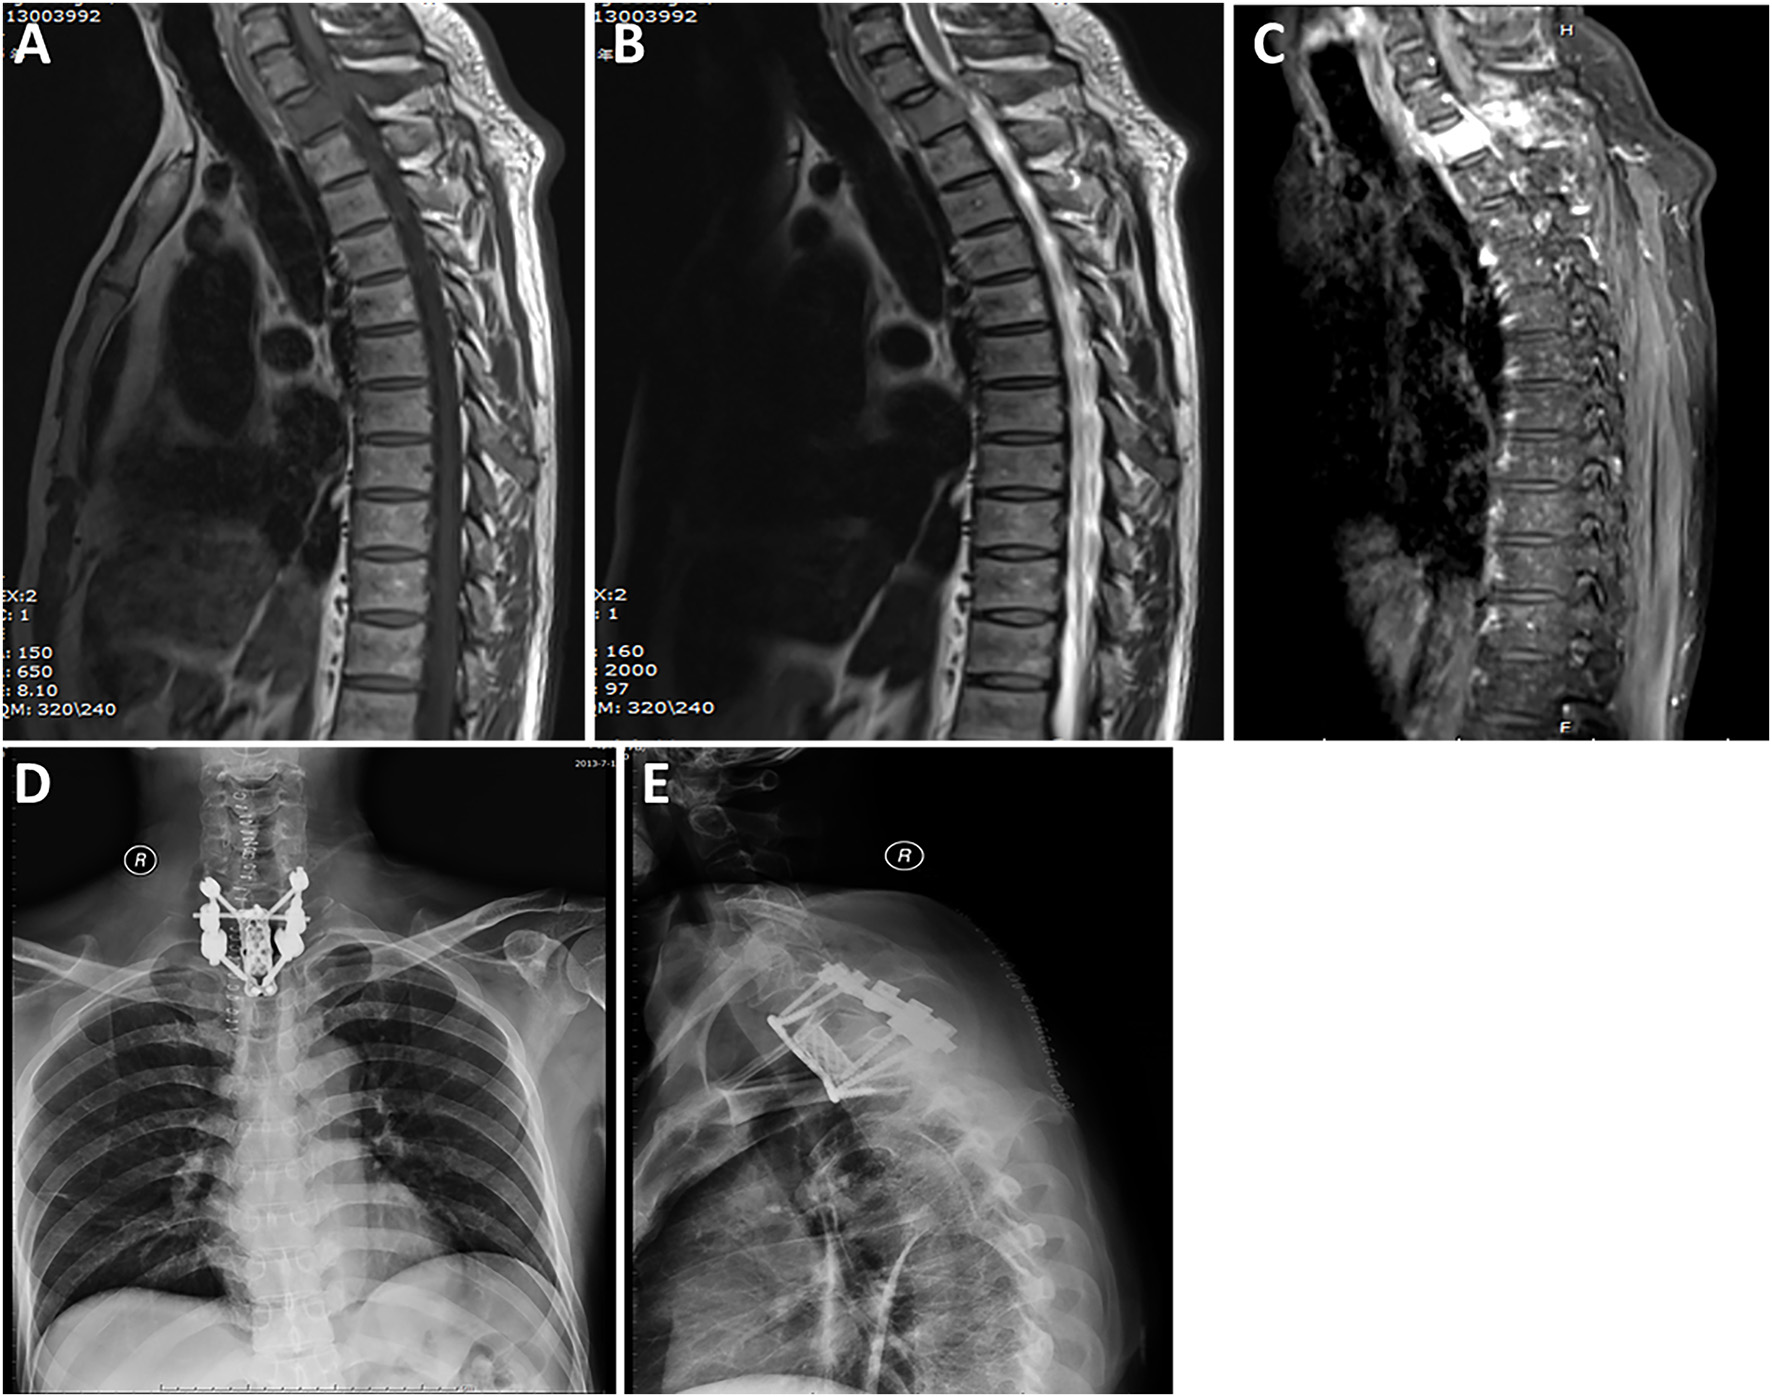

Radiological data are summarized in Table 1. Based on MRI scans, the lesions were hypointense (n = 35, 87.5%) or isointense (n = 5, 12.5%) on the T1-weighted images (Figures 1–3), and isointense (n = 8, 20.0%) (Figures 1, 2) or hyperintense (n = 32, 80.0%) on the T2-weighted images. Thirty-five (87.5%) lesions showed significant heterogeneous enhancement (Figures 1–3) and five (12.5%) lesions showed significant homogeneous enhancement on MRI scans. The lesions involved the cervical spine in six (15.0%) cases, thoracic spine in 24 (60.0%) cases, lumber spine in 13 (32.5%) cases, and sacrum in five (12.5%) cases, respectively. Among these cases, one case showed involvement of both the cervical and thoracic spines, three cases showed involvement of both the sacral and lumbar spines, and four cases showed involvement of both the thoracic and lumbar spines. In addition, tumor lesions involved a single segment in seven (17.5%) cases, and multiple segments in 33 (82.5%) cases. Seventeen patients were radiographed for intraspinal tumors and vertebral bone destruction (Figures 1, 2). Regarding the subtypes, the spinal canal type (Figure 1) was detected in 32 (80.0%) cases and vertebral type (Figure 2) was detected in eight (20.0%) cases.

Figure 2. A case labeled as vertebral type because the maximal diameter of the tumor was located in the vertebral body and accessory. Preoperative T1-weighted (A) and T2-weighted (B) images revealed a tumor at the T1 level. Contrast-enhanced sagittal (C) image revealed that the tumor showed significant homogeneous enhancement. Postoperative radiograph of the thoracic spine after surgery showing that the reconstructed thoracic spine was well-maintained. Anterior-posterior view (D). Lateral view (E).